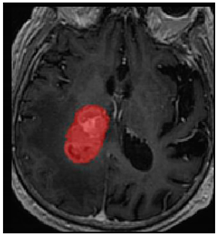

Three cases from the NTUH dataset showing representative results of different models were shown in Table 2, Table 3 and Table 4. The overall dice scores of these networks on the NTUH dataset ranged from 0.33 (DeepMedic) to 0.51 (V-Net). Table 5 shows the detailed performance of each network tested with the NTUH dataset.

Predictions with low dice scores.

Predictions with average dice scores.

Predictions with high dice scores.